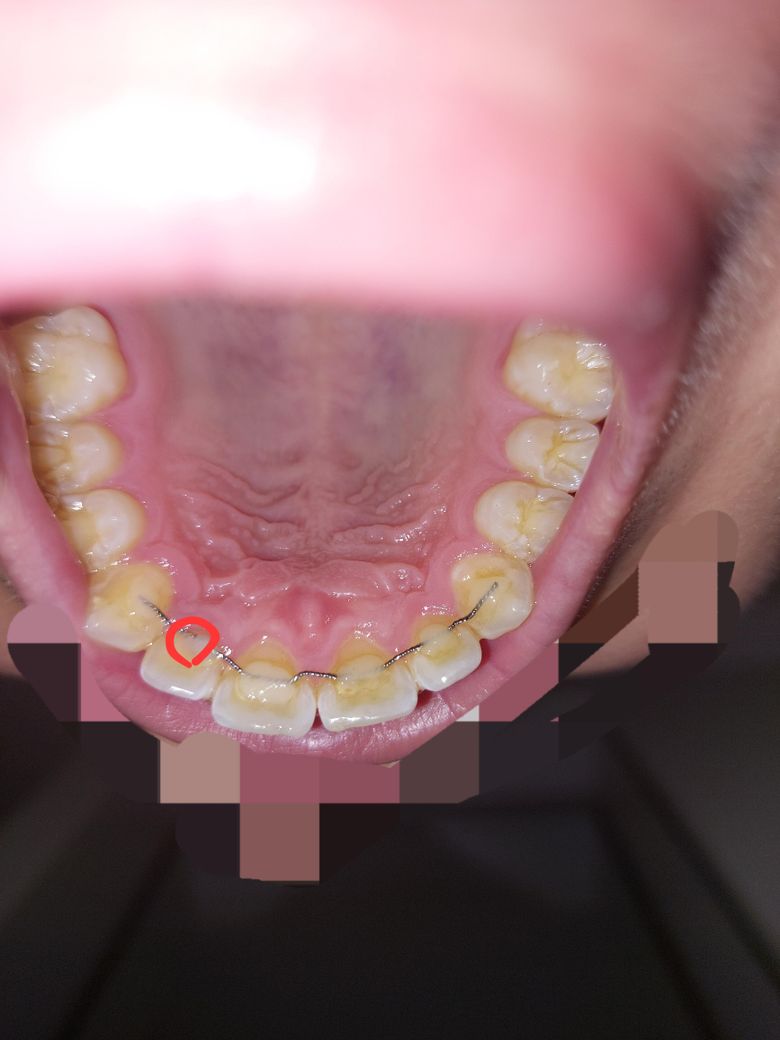

저는 교정끝난지는 7년차고 위 유지장치를 교정끝난직후 현재까지 부착하고있었는데 워낙 오래됐다보니 빨간색부분 철사가 절단됐다길래 아래사진처럼 절단된곳만 잘라내고 레진을 삭제해둔상태인데요.

• 1번 째 사진

• 2번 째 사진